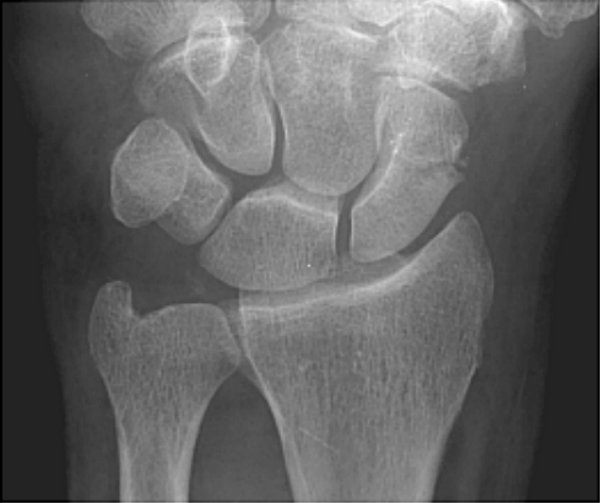

Return to Scaphoid Fracture